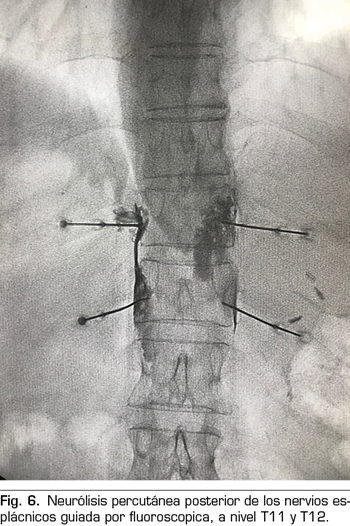

– Los nervios esplácnicos son tres nervios que nacen de la cadena simpática torácica y se disponen lateralmente en la columna vertebral: 1) el esplácnico mayor se forma por las fibras preganglionares simpáticas de T5 a T9; 2) el esplácnico menor se forma por las fibras procedentes de T10 y T11; y 3) el esplácnico inferior, por las fibras que vienen de T11 y T12. Todos ellos confluyen en la cara lateral de las vértebras T11 y T12 −lugar idóneo para la realización de una neurólisis− y discurren paralelos hasta atravesar el diafragma y unirse al plexo celiaco.

Se realiza mediante un abordaje posterior retrocrural, normalmente guiado por fluoroscopia (Figura 6). Las lesiones pueden llevarse a cabo mediante radiofrecuencia convencional o utilizando agentes neurolíticos como en el plexo celiaco.